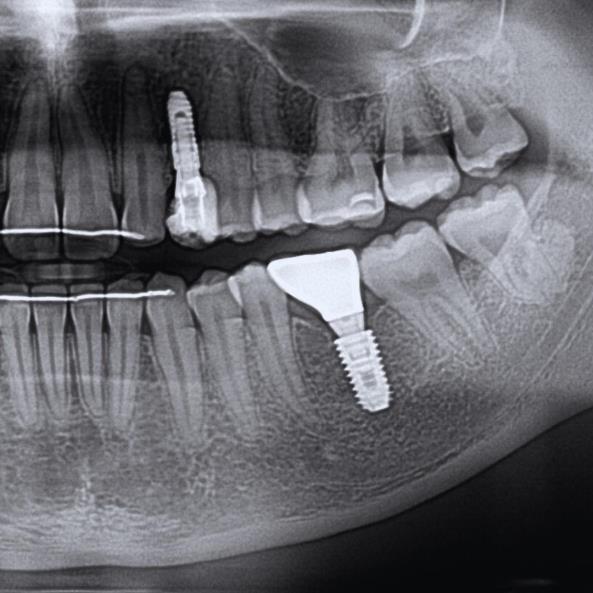

Çene kemiklerinde hacim yetersizlikleri ve kemik erimesi nedeniyle implant yaptıramayan birçok hastamızın tedavilerini, kemik greftleme (kemik tozu uygulaması) ile tamamladık ve böylelikle implant destekli sabit (takıp çıkarma gerektirmeyen)protezler kullanmaya başladılar.

Kliniğimizde kemik grefti tedavisi, eksik ya da yetersiz kemik dokusunu yeniden yapılandırmak için modern ve güvenilir yöntemlerle uygulanmaktadır. Özellikle implant planlanan vakalarda, kemiğin yetersiz olduğu durumlarda kemik grefti ameliyatı ile bölge güçlendirilir ve sağlıklı bir temel oluşturulur.

Kemik grefti iyileşme süresi, uygulanan yönteme ve hastanın iyileşme hızına bağlı olarak değişmekle birlikte ortalama 3–6 ay arasında tamamlanır. Bu süreç sonunda implant veya diğer tedavilere güvenle geçilebilir.